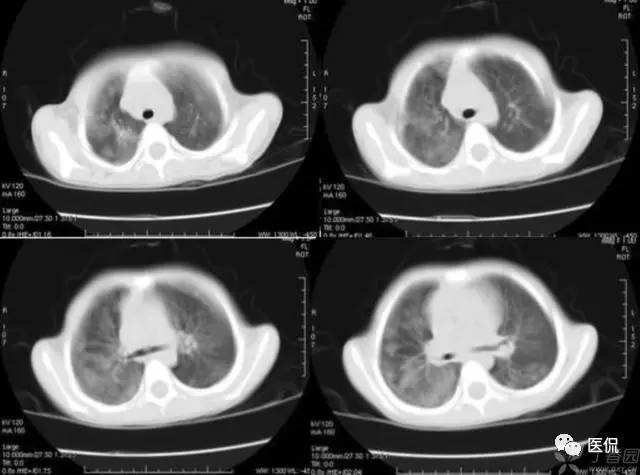

粘液支气管征又称为支气管液像,支气管粘液栓塞造成的CT征象。其病理基础是肺不张内有支气管粘液栓塞。由支气管狭窄梗阻、粘液分泌异常和纤毛活动障碍所致。对于中央型肺癌、狭窄或梗阻支气管的远端形成粘液铸型。支气管内膜结核有较长范围的支气管狭窄及支气管纤毛破坏使粘液不易排出。支气管分泌物增多也对粘液潴留起重要作用。慢性肺炎的支气管分泌物增多、粘稠及纤毛破坏是支气管粘液潴留的原因。CT增强扫描0表现为肺不张内未强化的管状或结节状低密度影,与支气管走行方向一致。

图1 变态反应性支气管肺曲霉菌病患者经治疗后右上肺浸润性病变大部分吸收。CT片上可见到树枝状粘液栓,其主轴指向肺门并与支气管的走向分布一致。支气管可见明显扩张 图2 左上肺肺癌患者,经细胞学检查证实。CT示肿瘤突入左主支气管,可见杯口状表现。其远端分支状支气管粘液栓清晰可见,轴向指向肺门。图3,4 支气管扩张患者反复多次咯出棒状和粉皮状粘液栓。CT示左下叶背段粘液栓,支气管也明显扩张(图3)。同一患者当粘液栓咯出后CT片可见扩张的支气管中间呈透亮带,横径比原粘液栓稍小,酷似鱼嘴状(图4)。

左图:治疗前的支气管粘液栓; 右图:治疗后粘液栓吸收,支气管通畅